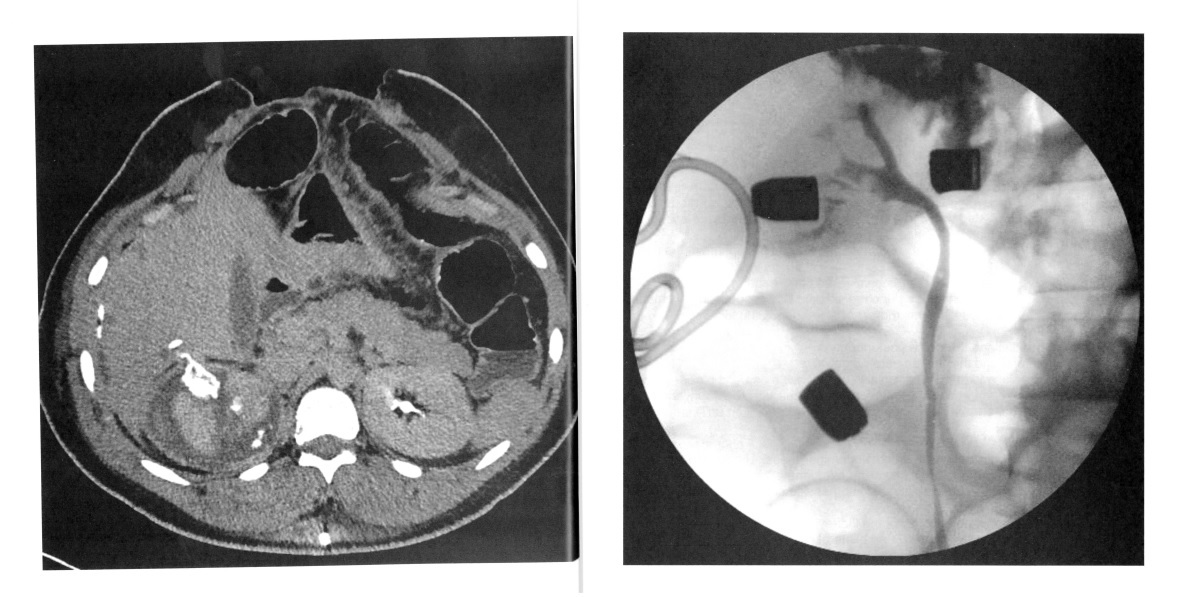

A 24-year-old man is shot in the right flank and sustains a grade 5 renal injury and extensive liver and bowel injury. During exploration, his liver and bowel injuries are stabilized and a nonpulsatile right retroperitoneal hematoma is identified with no intervention . One week after exploration, he develops increased drainage from a perihepatic drain. Creatinine of the drainage fluid is 8 mg/di. CT scan and retrogradepyelogram are shown. The next step is:

2

The patient has a delayed urine leak following high velocity penetrating renal trauma. CT scan and retrograde pyelogram reveal a urine leak. The next step is ureteral stent and urethral catheter drainage to prevent reflux of urine retrograde into the stent which may potentiate the leak and result in infection of the retroperitoneal hematoma. Ureteral stent placement may allow for resolution of the leak without operative intervention. The patient’s recent history of shattered kidney along with liver and bowel injury placement of a percutaneous nephrostomy tube would result in increased risk for infection of the perinephric hematoma and maybe difficult to place and maintain in the proper position due to the renal injury. Exploration of the right kidney is not ind icated at this time.